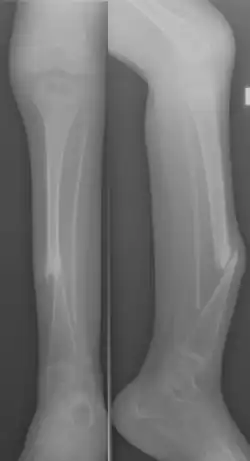

Congenital pseudarthrosis of the tibia (CPT) is a rare paediatric disease presenting with a bowing deformity of the tibia at birth or within the first decade of life.[1] It is most commonly associated with Neurofibromatosis type 1 (NF-1).[2] For children with CPT, pathological fracture of the tibia eventually occurs, resulting in persistent nonunion of the fracture site. If left untreated, leg deformities, joint stiffness, leg-length discrepancy and pain will persist.[3] Diagnosis is done clinically and through X-ray imaging, with numerous classifications based on the severity of bowing and presence of fracture or intraosseous lesion.[4]

Primary CPT presents at birth or in infants as anterolateral bowing of the tibia. Bowing is observed as shortening of the corresponding leg, and is confirmed with X-ray imaging. It is commonly presented unilaterally, but can be bilateral.[1][8]

Secondary CPT does not present with obvious bowing at birth and may be overlooked, but will eventually progress to pathological fracture as the infant grows. Approximately 50% of fractures occur before the patient is two years of age, when toddlers begin learning to walk.[1][8]

CPT is characterized by persistent nonunion because of fractures of the tibia and the presence of fibrous tissue between parts of the fractured bone. The persistent nonunion eventually leads to the formation of a false joint, otherwise known as pseudarthrosis. This pseudarthrosis is a non-healing bone lesion, resulting in reduction of mobility and persistent pain in the lower leg.[3]